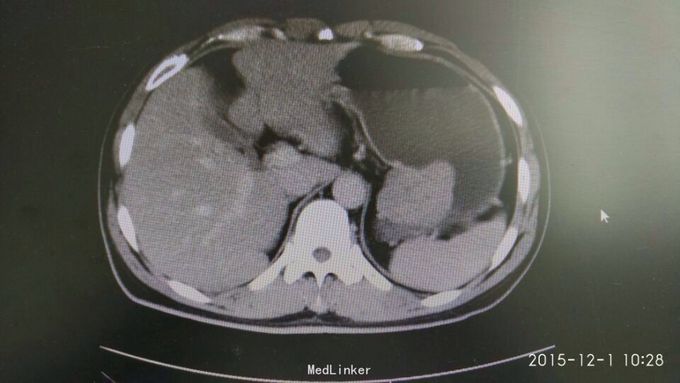

胃间质瘤 拟行胃间质瘤切除术

瘤体较大,超过5cm,术中注意与胰腺关系,如果压迫胰腺或压迫脾脏血管,是否考虑部分胰腺切除及脾切除,是否考虑胃空肠吻合。